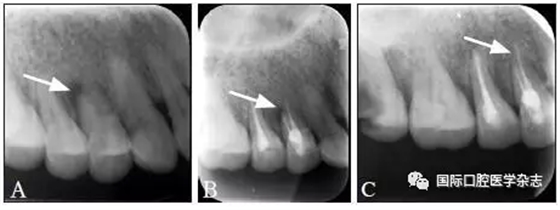

典型病例1 14牙因頸部楔狀缺損穿髓致根尖周炎,根管治療后根尖周透射區(qū)骨質(zhì)修復(fù)(圖1)。

A:初診X線片;B:充填后即刻X線片;C:13個(gè)月復(fù)查X線片。

圖 1 14牙根尖周炎經(jīng)根管治療后愈合

Fig 1 The healing of the tooth 14 with periapical periodontitis after endodontic therapy